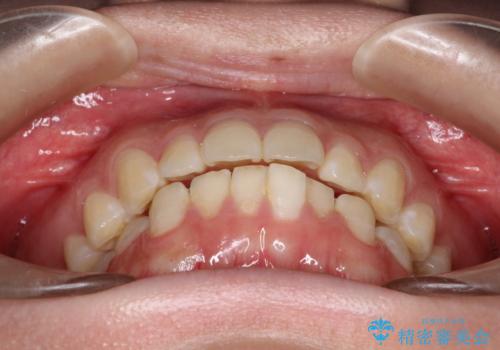

- 横から見たときの口元が出てるの気になるとのことで来院されました。

口元の突出感と口唇の閉じずらさが確認されました。

上下左右の歯を1本ずつ、合計4本抜歯しして前歯を後方に下げて、口元の突出感を改善する計画としました。

前歯をしっかり下げることで、口元がすっきりしました。